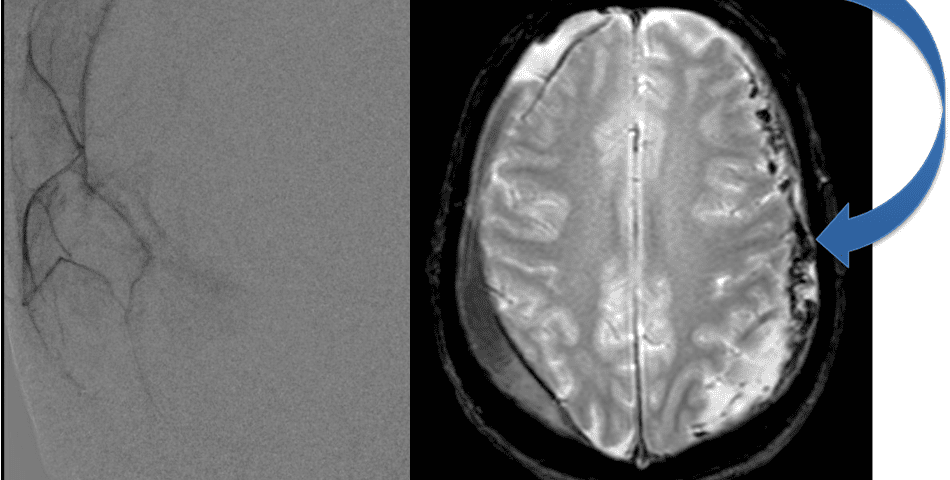

The patient agreed to receive minimally invasive treatment with Bilateral Middle Meningeal Artery Embolization, a new approach to promote resorption of chronic and subacute subdural hematomas in patients that are not improving with conservative measures or have contra-indications to surgical evacuation. Selective catheterization of the Middle Meningeal Artery is followed by transarterial embolization of the territory and inflammatory membranes that are felt to be secreting serosanguinous proteinaceous exceeding the capacity for resorption. MMA embolization was performed bilaterally in this patient. (Figure 2. A and B)

Figure 2. A) Initial right ECA angiogram ; B) Post MMA Embolization; C) Selective Embolization Of Middle Meningeal Artery Membranes using PVA particles (arrows).

Although conventional surgical methods, such as burr hole irrigation or observation in asymptomatic or minimally symptomatic patients have been the mainstay of treatment, middle meningeal artery (MMA) embolization has emerged as a promising adjunctive or alternative treatment. MMA embolization is a neuroendovascular technique which involves placing a microcatheter into the Middle Meningeal Artery, most commonly on the side of the cSDH (occasionally, bilateral embolization has been recommended for larger or bilateral collection. Embolization of both the anterior (frontal) and posterior (parietal) division is performed using a variety of embolic materials (liquid NBCA, Onyx, coils), although polyvinyl alcohol particles of <250 microns are most commonly used to achieve distal penetration and occlusion of the pre-capillary and capillary beds. The micro-leakage of blood and transudative proteinaceous inflammatory fluid in these inflammatory membranes is creating an imbalance in cycle of resorption and preventing resolution or promoting recurrence or growth of these cSDH collections and associated mass effect and midline shift.

Figure 7. Neovascularized membranes within cSDH

Care must be taken to place the microcatheter within a safe position for embolization, with special attention to potential collateral branches to the orbit/eye via sphenoid or meningo-lacrimal branches (which may cause vision loss) or petrosal branches supplying the geniculate ganglion, the tympanic portion of the facial nerve, and often the trigeminal nerve via a branch coursing along the greater petrosal nerve. Once a safe position in the main trunk of the MMA, or superselectively in each of its divisions is achieved, embolization is performed until stasis of contrast and dense contrast staining of the dura is observed within the embolized vascular beds.7

Figure 8. Dense contrast staining of vascular membranes during embolization.